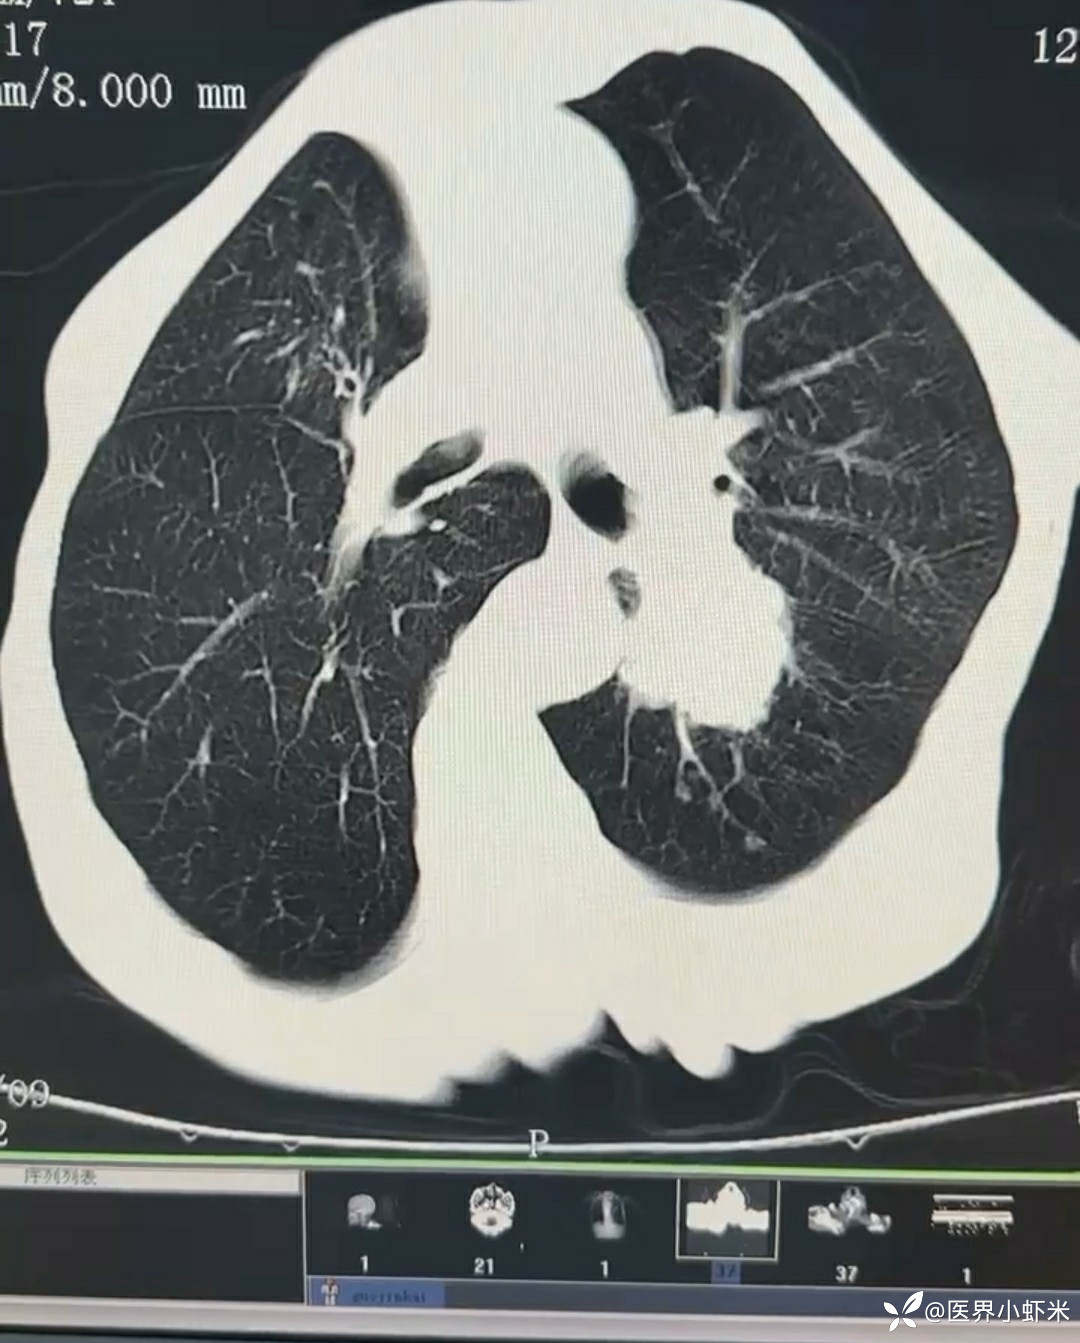

目前考虑:1.中央型肺癌伴2.肝继发恶性肿瘤?2.左丘脑继发恶性肿瘤?3.左丘脑出血?4.肾功能不全5.肝功能异常6右肾萎缩7.肺部感染8.慢性阻塞性肺病7.高血压3级(极高危)。